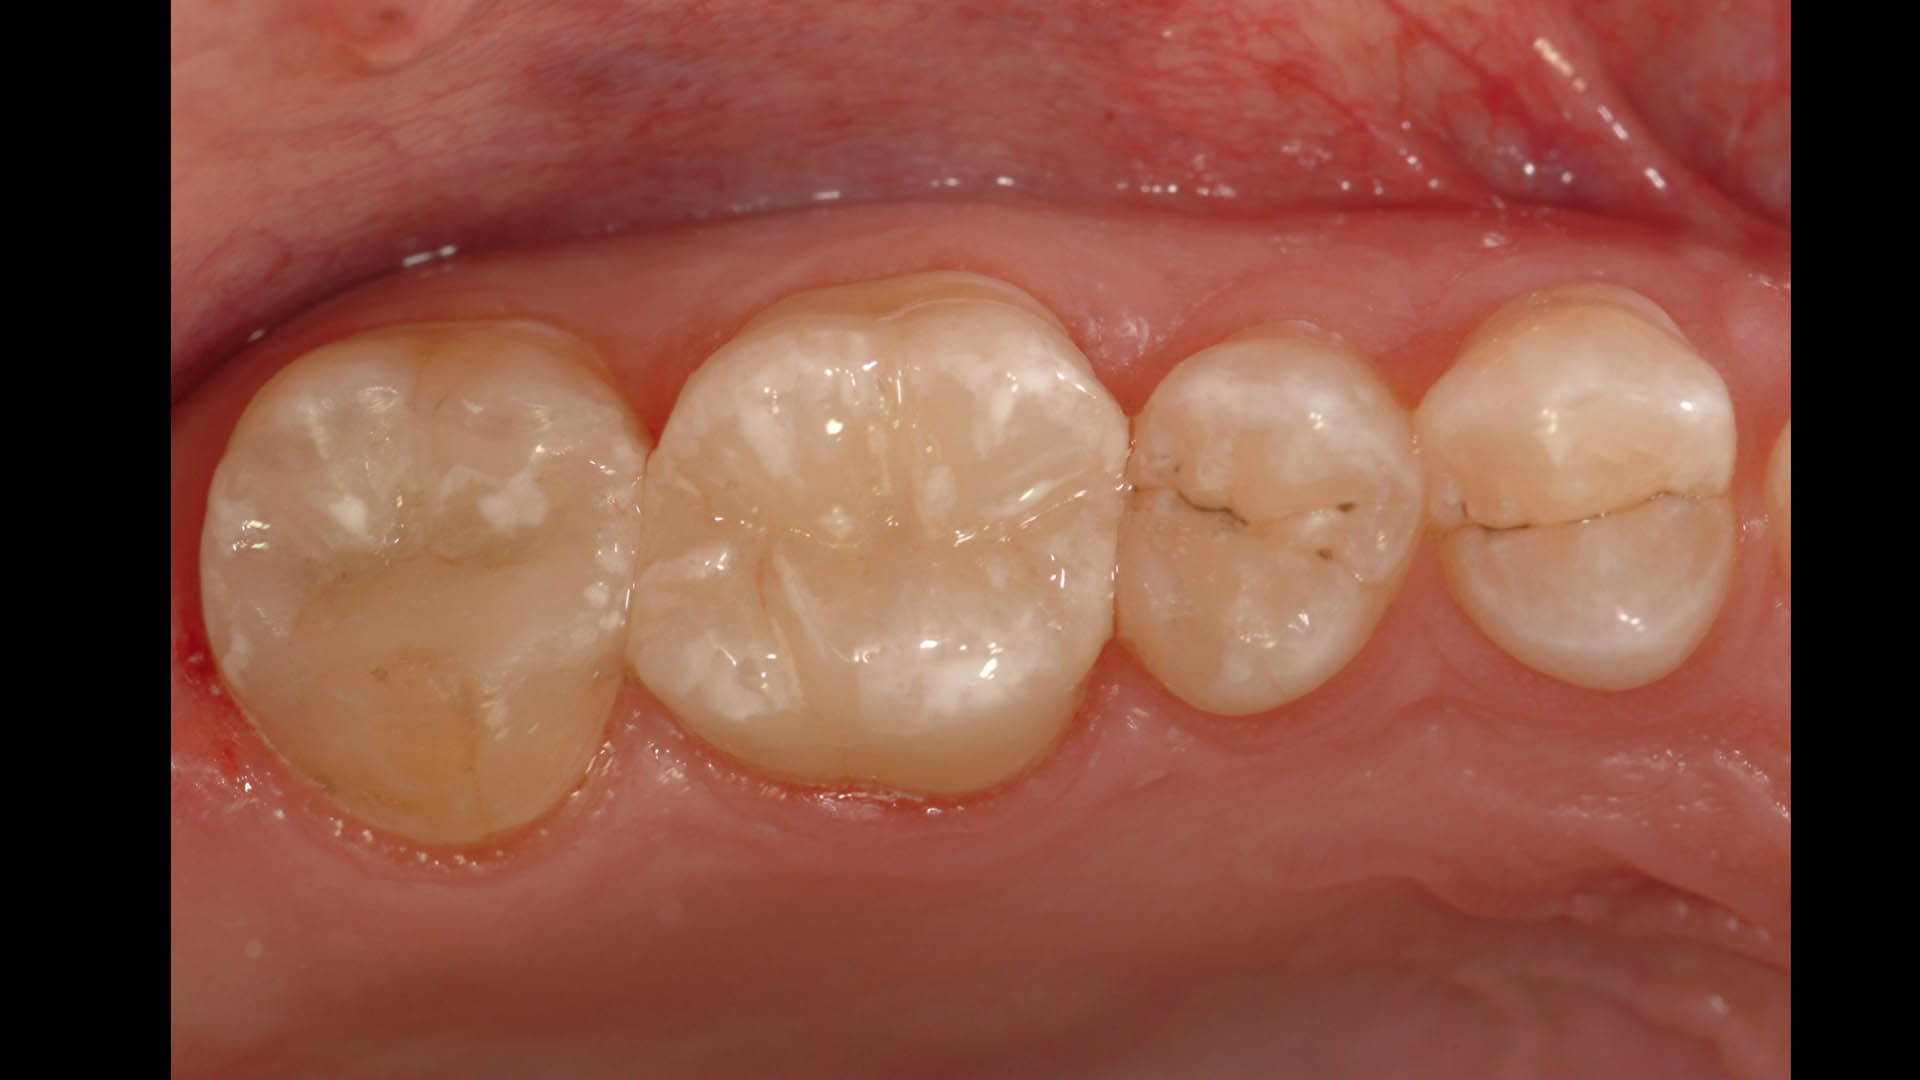

Take a glimpse into the magic of Coral Gables Dentistry through our before and after pictures. See firsthand the incredible smile makeover transformations that have brought confidence and joy to our patients.